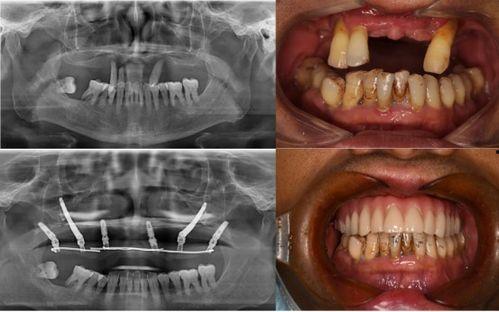

佛山种牙爆料事件最新情况,最新进展与各方回应梳理

最近佛山那边的种牙事件可是闹得沸沸扬扬的,咱们得好好来聊聊这个话题。你有没有听说,佛山某口腔医院因为种牙问题引发了一场不小的风波?别急,让我带你一探究竟,看看这背后到底隐藏着怎样的秘密。一、事件起因:患者反映种牙后问题不断话...